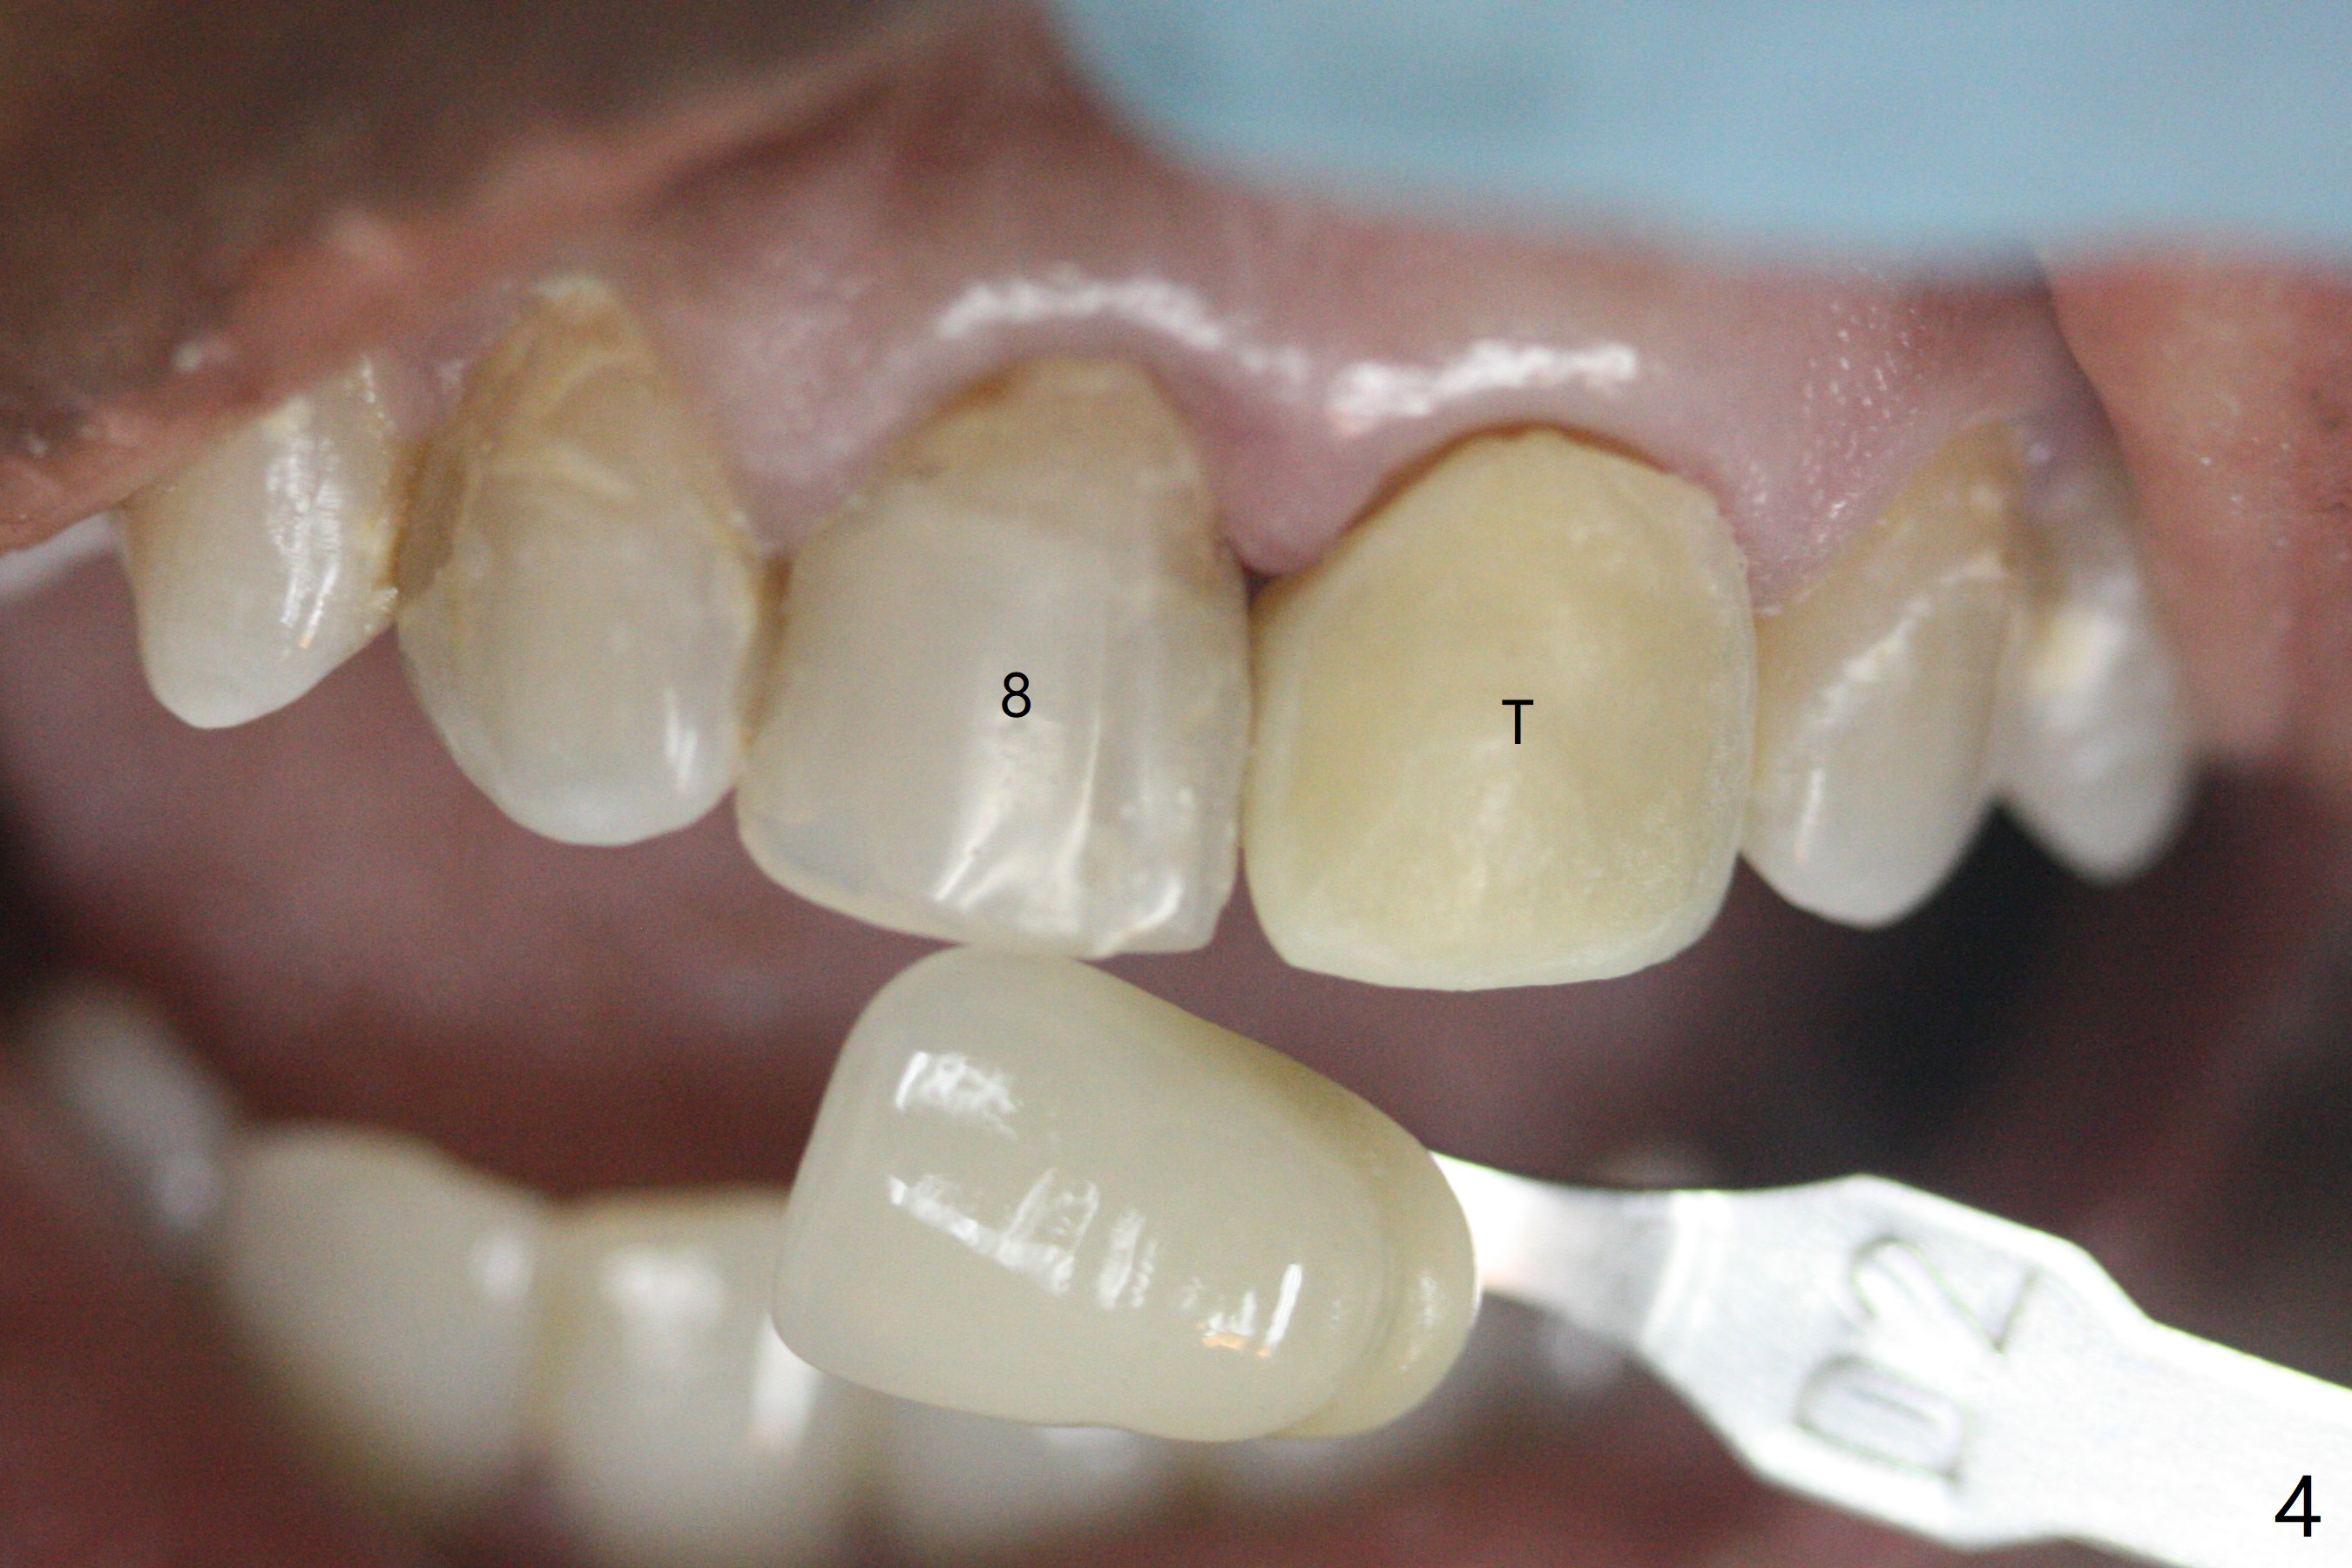

36岁女,9号牙树脂修补多次(图一),最近对冷热敏感,计划牙冠制备(如果不再敏感,再约一次与8号牙一起制备取模;如果敏感,9号牙根管治疗),使用Polycarbonate

Crown(图二,三)和Bosworth Trim II (Temporary Resin Acrylic

(D3)做内衬里)做临时牙冠。由于前者显得黄,而病人牙齿灰,她突然不满意,后来我们把临时牙冠表面磨掉,用Temporary

Resin Acrylic (D3)做外衬里(图四,五),勉强过关。大家如何处理这个难题?能买到类似Omnichrome树脂(composite)临时牙冠外壳?反映下面牙齿颜色。海平:临时牙冠facial